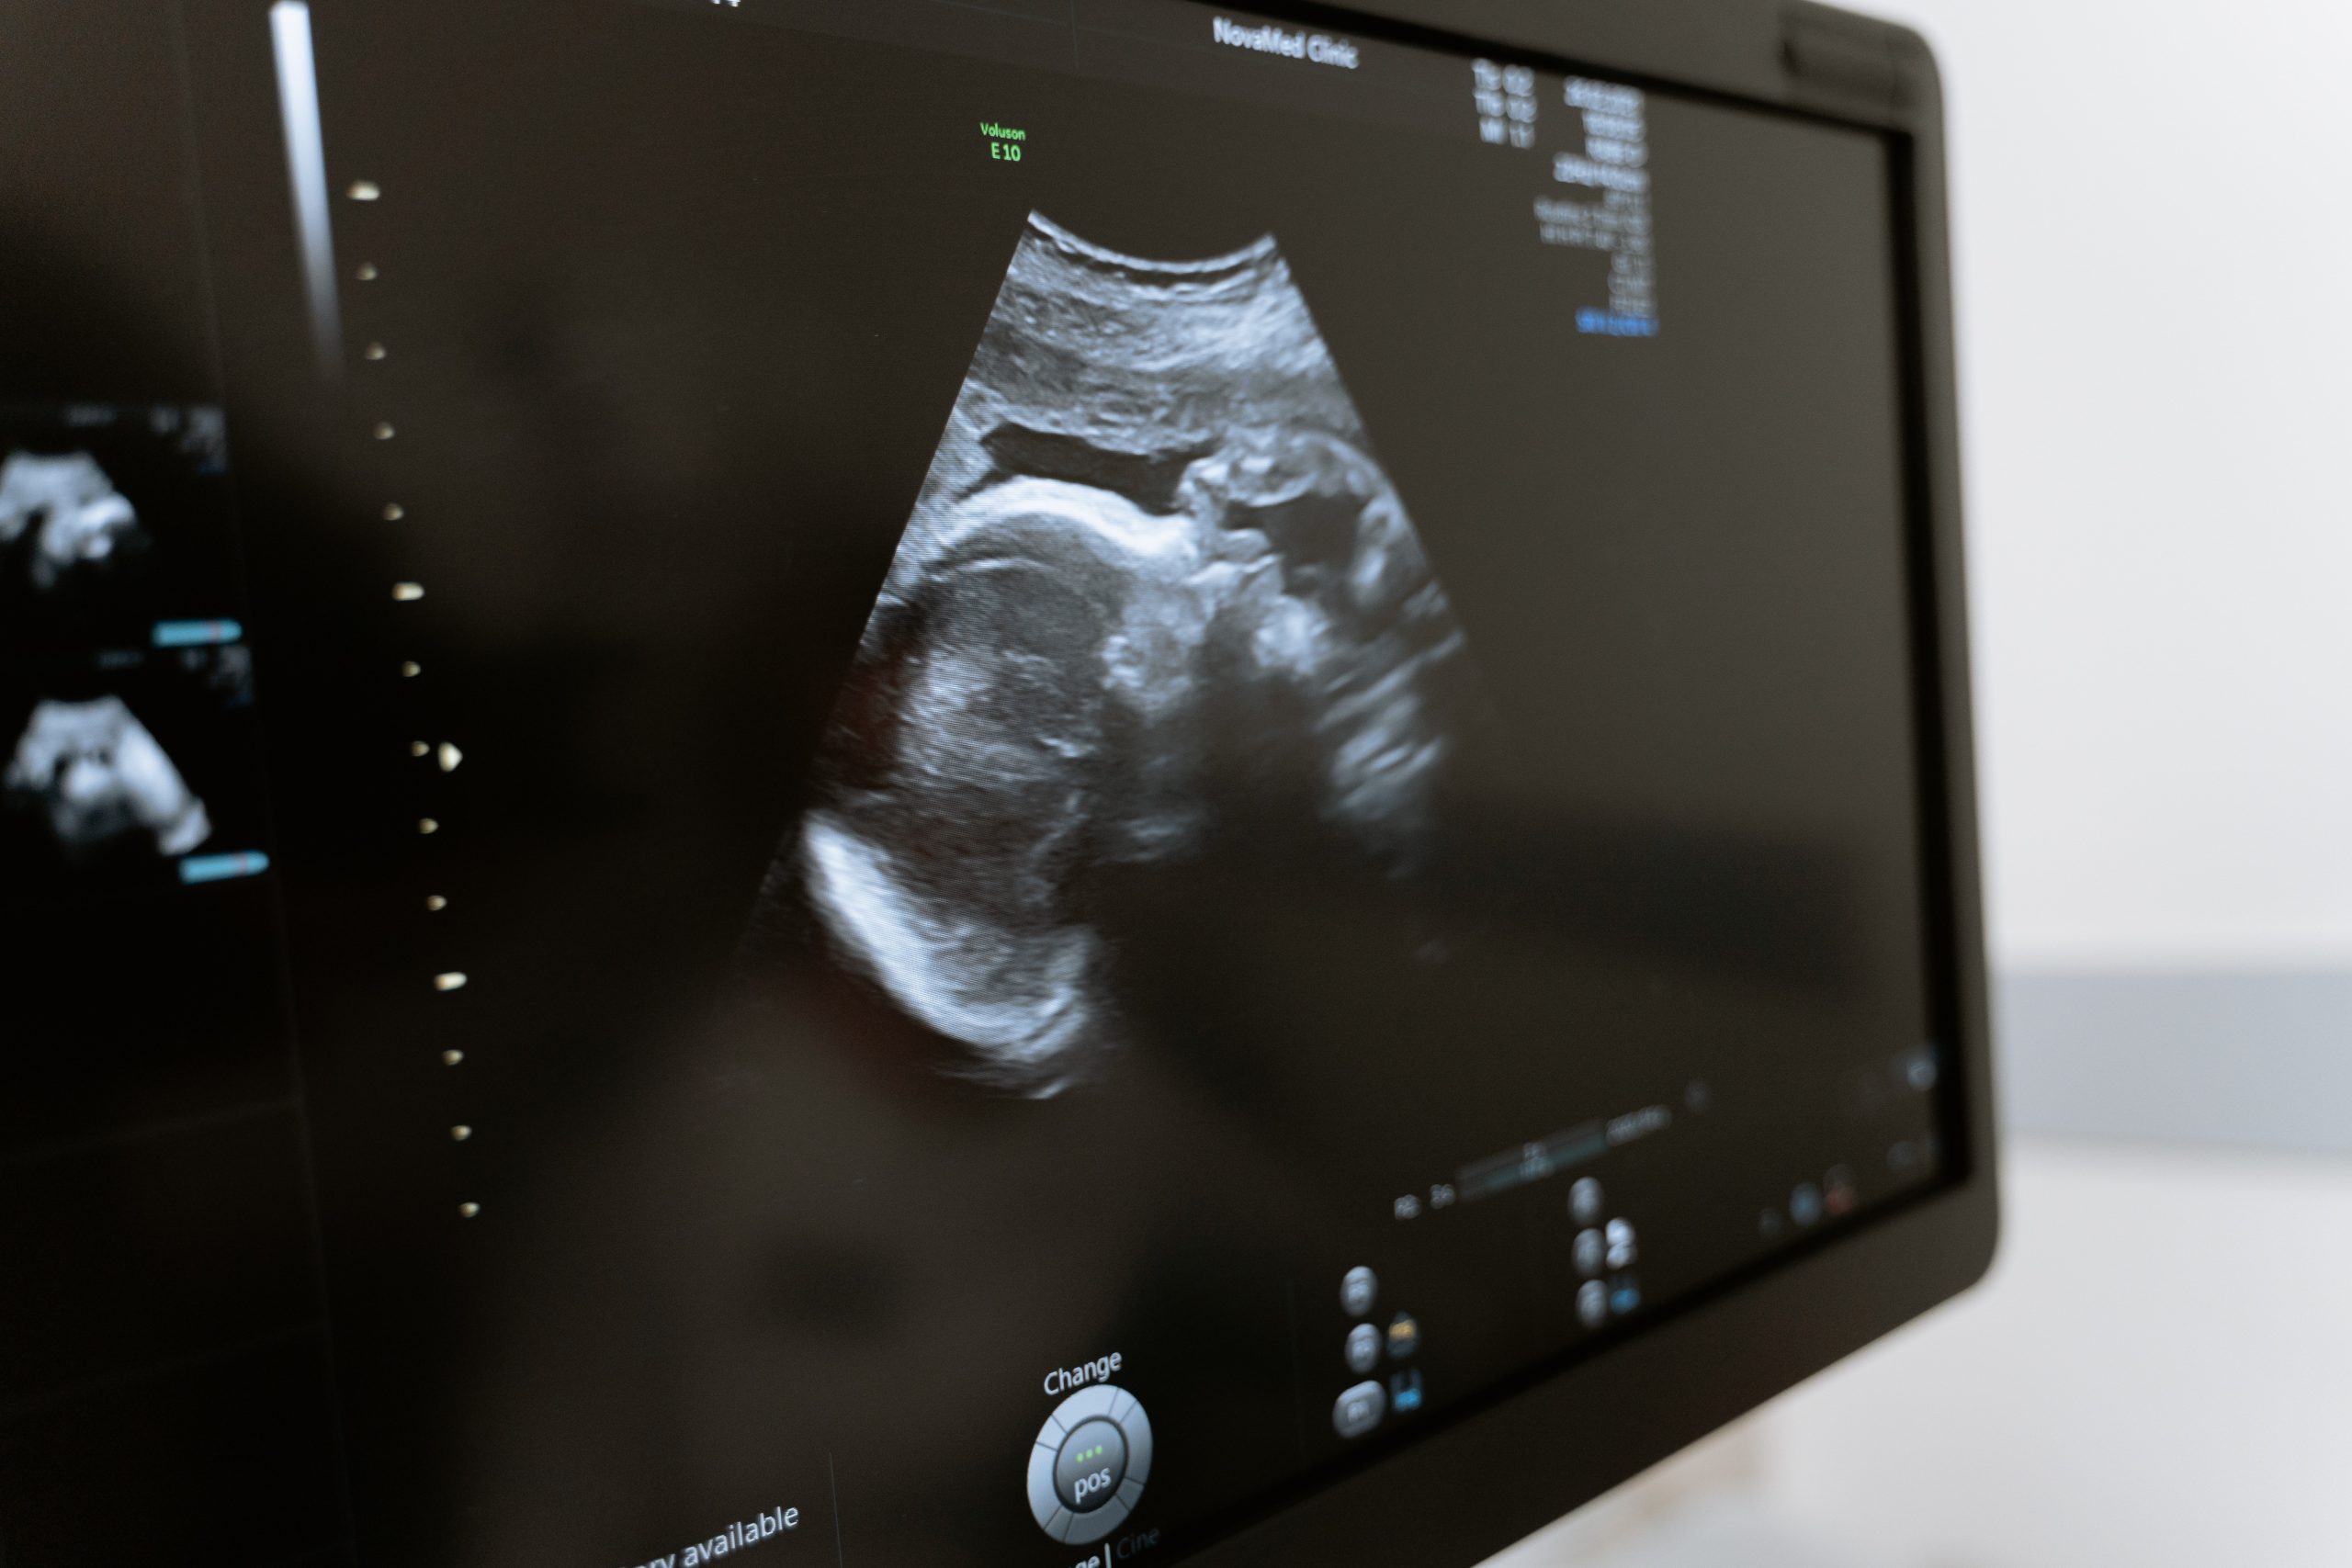

الصيام للحامل .هل الصيام آمن أثناء الحمل؟

لا يوصى بشكل عام للنساء الحوامل بالصيام دون إشراف طبي، لأن الصيام يمكن أن يحرم الأم والجنين من العناصر الغذائية الأساسية.

أثناء الحمل، من المهم استهلاك ما يكفي من السعرات الحرارية والبروتين والفيتامينات والمعادن لدعم نمو الجنين وتطوره. يمكن أن يزيد الصيام أيضًا من خطر الإصابة بالجفاف وانخفاض نسبة السكر في الدم ومضاعفات أخرى

ولكن يعتمد الصيام للحامل من عدمه على الرجوع للطبيب المختص بمتابعة الحامل وعلي تقييمه لحالة السيدة وعلي حالة الجنين